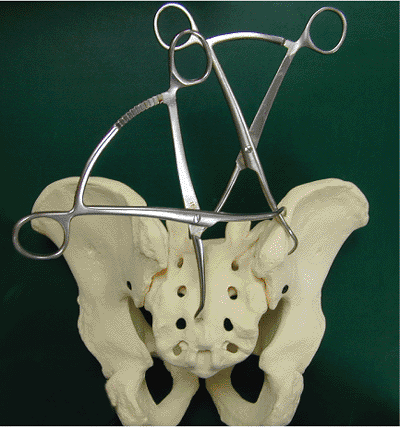

Figure 40.6.

Clamp placement shown on a sawbone model of a transforaminal sacral fracture. One clamp is used to control cranial displacement of the hemipelvis. The more transversely oriented clamp helps compress the fracture. |